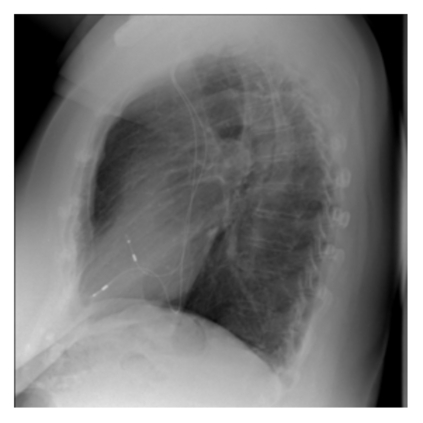

The evaluation of infectious disease processes on radiologic images is an important and challenging task in medical image analysis. Pulmonary infections can often be best imaged and evaluated through computed tomography (CT) scans, which are often not available in low-resource environments and difficult to obtain for critically ill patients. On the other hand, X-ray, a different type of imaging procedure, is inexpensive, often available at the bedside and more widely available, but offers a simpler, two dimensional image. We show that by relying on a model that learns to generate CT images from X-rays synthetically, we can improve the automatic disease classification accuracy and provide clinicians with a different look at the pulmonary disease process. Specifically, we investigate Tuberculosis (TB), a deadly bacterial infectious disease that predominantly affects the lungs, but also other organ systems. We show that relying on synthetically generated CT improves TB identification by 7.50% and distinguishes TB properties up to 12.16% better than the X-ray baseline.